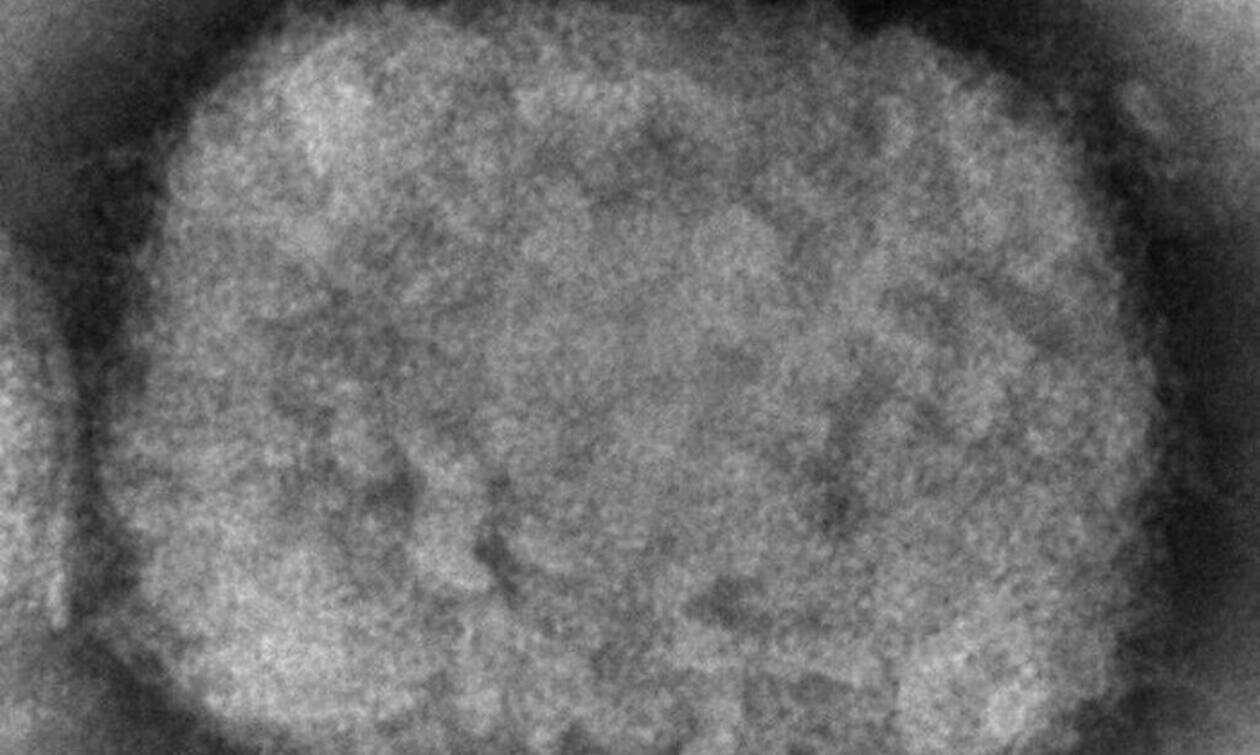

Η ευλογιά των πιθήκων δεν εξαπλώνεται τόσο εύκολα όσο η covid και υπάρχουν εμβόλια και θεραπείες για τη νόσο

Η ευλογιά των πιθήκων δεν εξαπλώνεται τόσο εύκολα όσο η covid και υπάρχουν εμβόλια και θεραπείες για τη νόσο, κάτι που δεν συνέβαινε με τον νέο κορονοϊό όταν πρωτοεμφανίστηκε. Ωστόσο έχει προκαλέσει ανησυχία.

Η ιογενής ασθένεια που προκαλεί συμπτώματα που μοιάζουν με της γρίπης και δερματικά είναι ενδημική σε κάποιες περιοχές της Αφρικής. Στην ήπειρο έχουν καταγραφεί περισσότερα από 1.500 ύποπτα κρούσματα από την αρχή του 2022, από τα οποία τα 66 ήταν μοιραία, σύμφωνα με τα επίσημα στοιχεία.